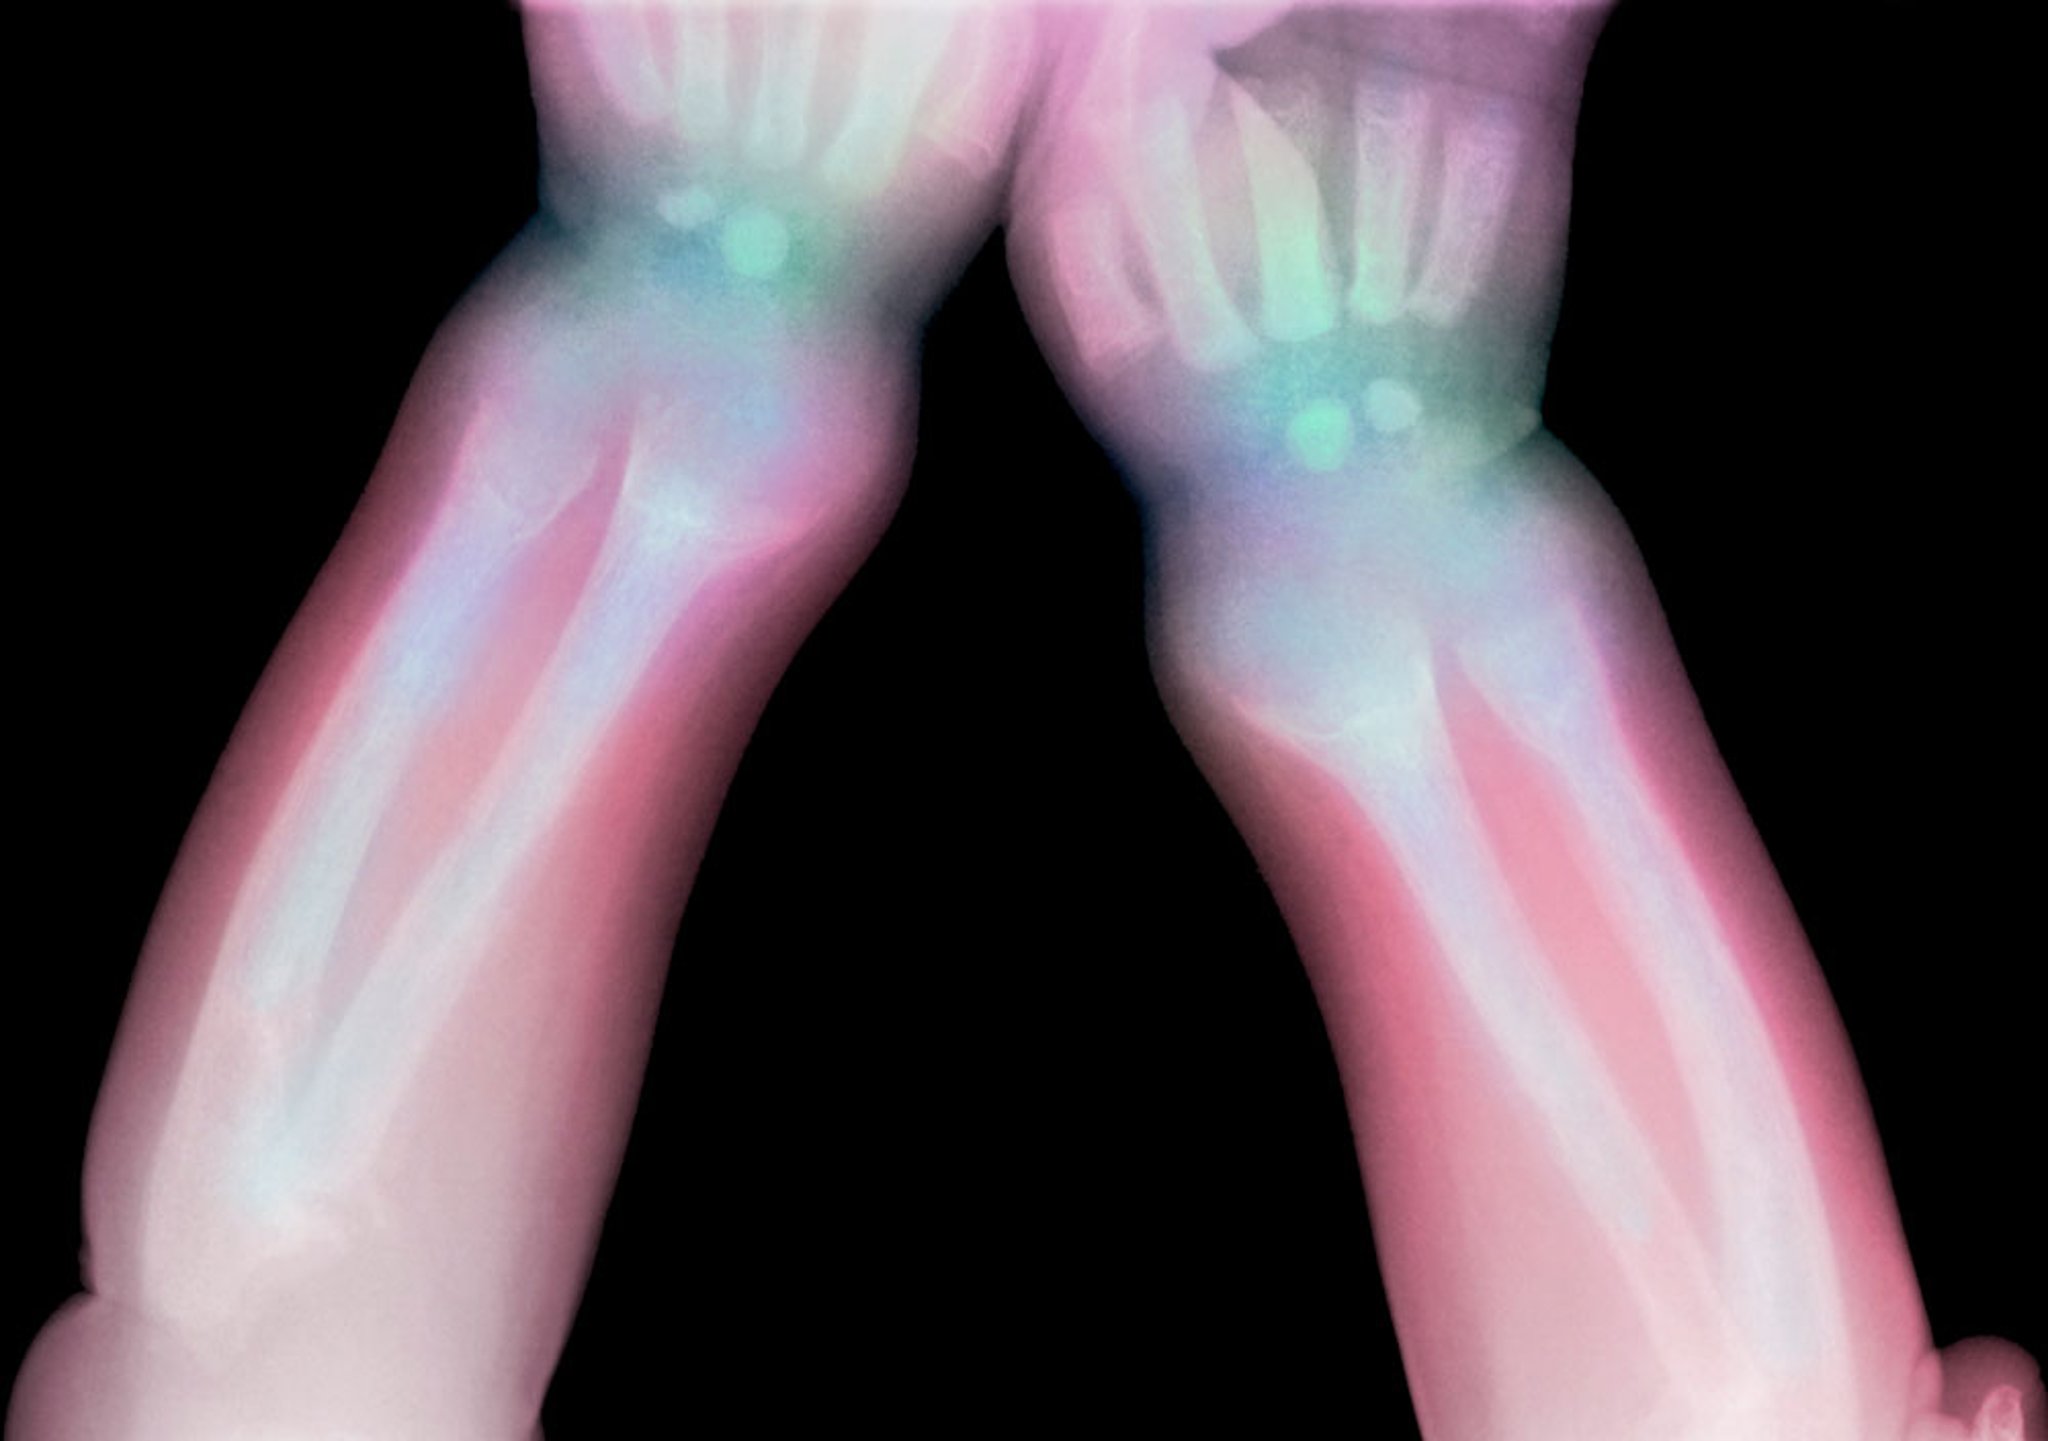

Rachitis

Diese Röntgenaufnahme zeigt die Transparenz des distalen Radius und der Ulna bei einem Kind mit Rachitis.